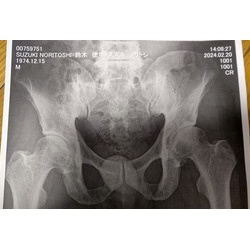

筋トレ日記2023~2024⑤~変形性股関節症 2024年03月08日 ここまで上半身のトレーニングはほぼ順調に進んでいるのですが、 1月より脚のトレーニングは股関節の痛みのため完全中止しております。 例年だとトレーニングを1か月ほど中止すれば再開できていたのですが、 今年はなかなか良くなる気配がありません。 そこでトレーナー ... もっと読む